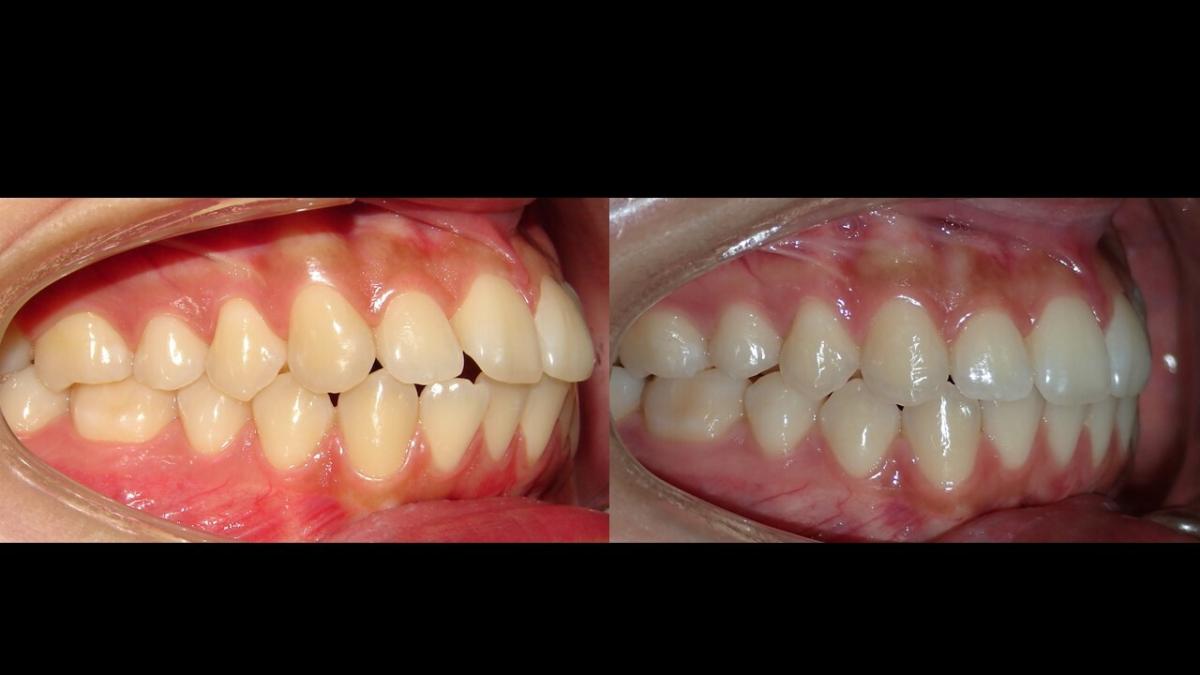

large-Resultado de avance de la mandibula

large-Avance de mordida